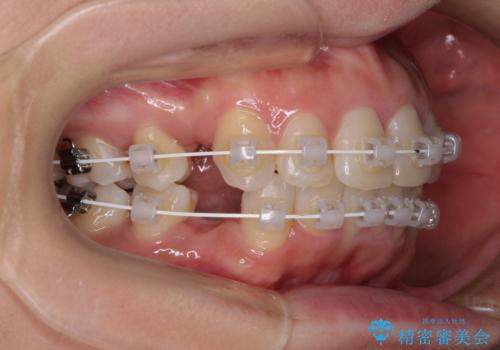

インビザラインが続けられない ワイヤー装置による抜歯矯正

- 上の前歯の飛び出した感じと上下前歯のデコボコを気にして来院された患者様です。

叢生が強く、口元の突出感もあるため、上顎左右第一小臼歯4本を抜歯することとしました。

奥歯の咬み合わせ改善が必要なため、ワイヤー装置による矯正治療を強くお勧めしまたが、本人の希望でインビザラインにて治療を開始することとなりました。

インビザラインでの抜歯治療は予定通りに治療が進まないことが多いため、必要であればワイヤー矯正に切り替えるとお伝えした上で治療を開始しました。

2年ほどインビザラインを使用しましたが、どうしても歯の移動がマウスピースに追随せず、全顎ワイヤー矯正へ切り替えました。

ワイヤー装着後は2年弱で、しっかりと仕上げることができました。